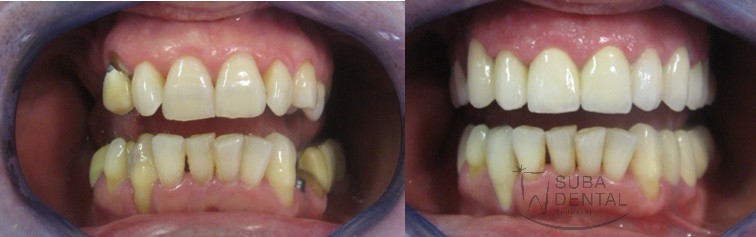

Before After